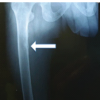

A 52-year-old female lawyer, Caucasian, came to our clinic complaining of bilateral forefoot pain for 2 weeks. Her referred symptoms have arisen after a 20 km run of an amateur race. She was used to running 10 km per week as an amateur runner. She denied any relevant trauma or joint sprain. She described the pain increasing during walking or jumping and decreasing at rest. She was ambulatory without any supporting tools. She had been taking non-steroidal anti-inflammatory drugs with mild benefits. The patient had no relevant medical history, and she was not taking any other medications or supplements. On physical examination, she had local swelling without erythema over the first metatarsal dorsum bilaterally, especially on the medial side. Tenderness to palpation was noted in this area as well. She suffered moderate pain during gait and the flexion and extension of the first metatarsal-cuneiform (Lisfranc’s) joint. The pain did not modify with ankle or significant toe motion, neither passive nor active. She had a bilateral unpainful, non-rigid hallux valgus (HVA), more pronounced on the left foot. No other foot deformity was detected. She was 165 cm tall and weighed 56 kg (body mass index 20.6 kg/m2). X-ray of both feet showed linear sclerosis, perpendicular to the diaphysis of the first metatarsal, approximatively in the half of the bone. Signs of osteoarthritis of the first metatarsal-phalangeal were also detected bilaterally. HVA bilateral was confirmed (on the left foot, HVA angle 25° and intermetatarsal angle (IMA) 16°, on the right foot HVA 27° and IMA 12°) (Fig. 1).